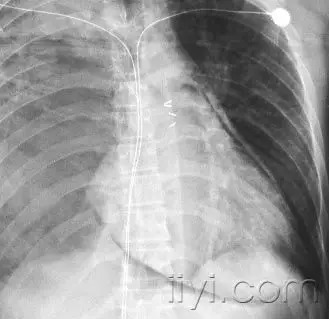

空气新月征 医学百科网 | YxBaike.Com

平片和CT:空气新月征是空洞壁与内部团块之间的新月形气体积聚。空气新月征是既存空洞内曲菌球形成,或者侵袭血管性曲菌病肺梗死后收缩的特征性表现。但是在其它情况下,也可以出现空气新月征,例如结核、伟格氏肉芽肿,空洞出血或者肺癌。